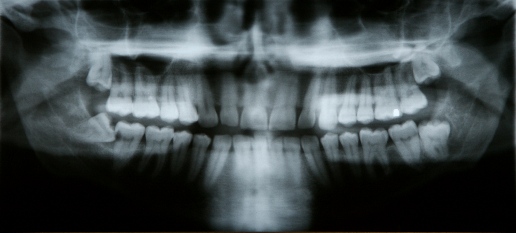

A tooth becomes impacted when there is not enough room to accommodate the space in the dental arch and growth becomes impossible. After surgery to remove an impacted tooth, mild discomfort and some swelling is expected. This is part of the process and should not alarm you. You may use cold compresses to alleviate the swelling. In addition, your doctor will prescribe pain medication, which should be taken as directed. Patients are also advised to favor the tooth extraction area and modify their diet for a few days to allow for healing. For personalized post-operative care and support, bloom family dentistry is here to ensure your recovery is smooth and comfortable.